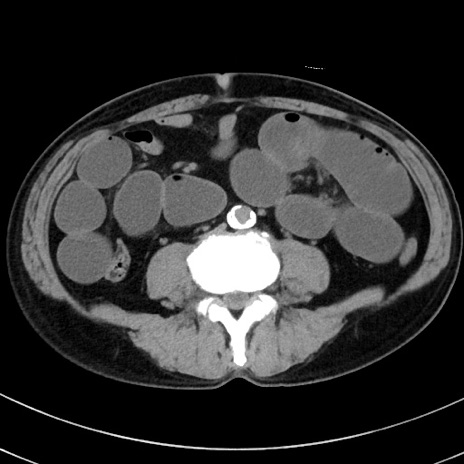

症例38(横断像)

【症例】70歳代 男性

【主訴】腹痛・嘔吐

【現病歴】昨晩より、嘔吐・腹痛あり。今朝になっても嘔吐あり。来院。

【既往歴】心臓バイパス手術、開腹胆摘、腸閉塞

【身体所見】BP 107/71mmHg、HR 116/min、腹部:平坦、軟、下腹部に軽度圧痛あり。反跳痛なし。

【データ】WBC 15100、CRP 0.32